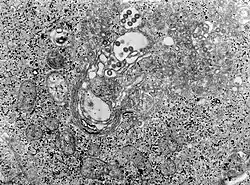

| TEM micrograph of tissue infected with Rift Valley fever virus | |